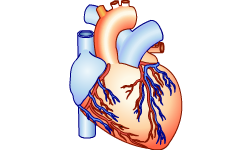

Vraag 14

Bekijk de afbeelding.

Wat zie je?

Bij welk orgaanstelsel hoort het hart?